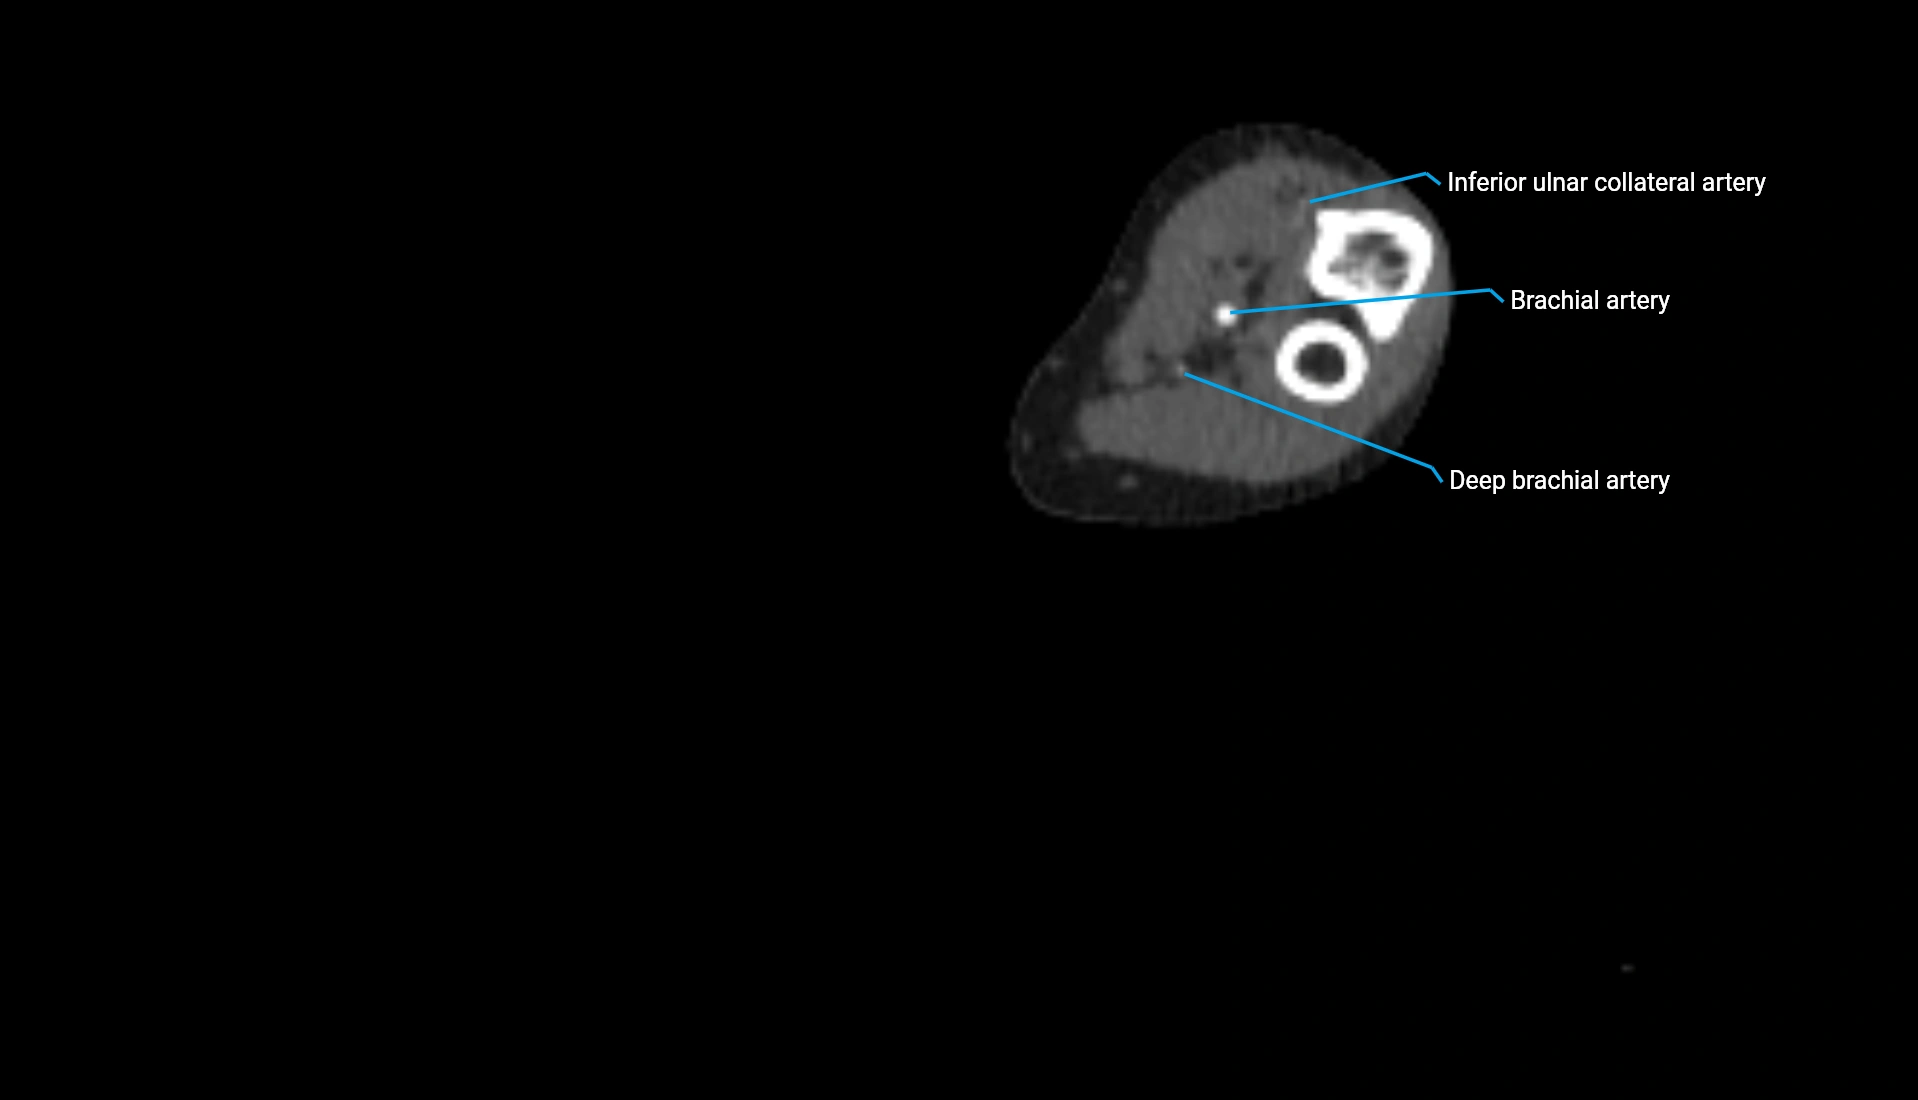

CT Appearance

Non-Contrast CT:

• Cortex: High-density, sharply defined

• Subchondral bone: Dense cancellous matrix

• Articular surface: Smooth concave contour articulating with the capitellum

• Excellent for evaluating bone integrity, alignment, and subtle fractures